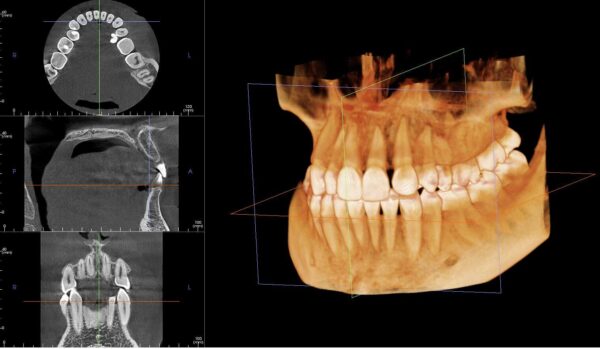

3D рентген зуба, или, как его часто называют, конусно-лучевая компьютерная томография (КЛКТ), — это высокотехнологичная методика, которая позволяет получить трёхмерное изображение ваших зубов, десен и даже челюстей. Это не просто обычный рентген. Он позволяет стоматологам увидеть более полную картину состояния полости рта, что очень важно для диагностики.

Такая техника значительно ускоряет процесс обследования и помогает врачу лучше понять, что происходит с зубами пациента. В отличие от традиционных рентгеновских снимков, которые могут показывать только в двух измерениях, 3D рентген сосредотачивается на том, чтобы обеспечить полноценный обзор в объеме. Это особенно полезно при планировании имплантации зубов, лечения кист или сложных ортодонтических случаев.